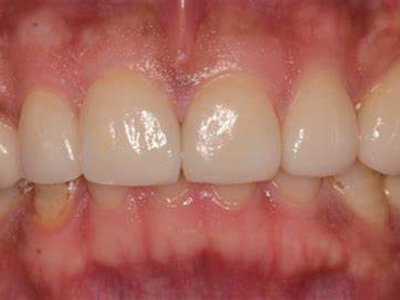

牙龈退缩上排多颗牙的牙根暴露图

牙龈退缩导致上排多颗牙齿的牙龈回缩,部分牙根暴露在外,伴有牙齿松动、口臭等症状,是由于牙周炎、局部受力过大等因素导致。